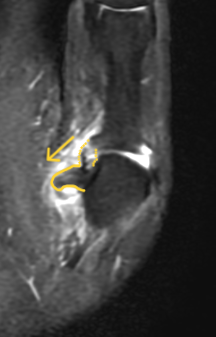

O exame de RNM deve ser solicitado para diagnóstico e para definir o grau de lesão do ligamento colateral ulnar do polegar. Na imagem, é possível visualizar o ligamento, o grau de ruptura das fibras e se há interposição de estruturas (geralmente a aponeurose do adutor do polegar) entre o ligamento e a sua inserção, definindo a lesão de Stener.